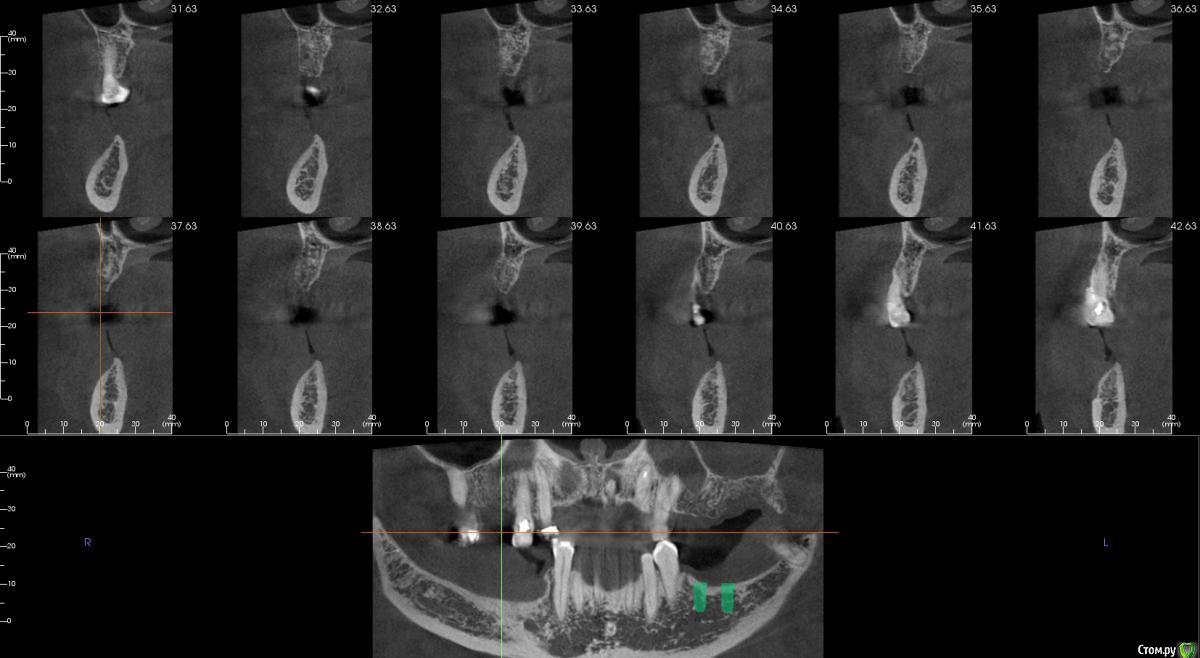

kamranchick Опубликовано 17 февраля, 2015 Поделиться Опубликовано 17 февраля, 2015 Добрый вечер.Имеется следующая проблемаПациент обратлся с жалобами в области отсутствия жевательных зубов, планируется имплантация.Вопросы такого плана, в области 3 сегмента думаю сделать расщепление гребня, установка имплантов 3,75/8 и аугментация костью Ostebiol Gen-Os, мембрана.В области 4 сегмента больше сомнения, планируется титановая сетка +аугментация, либо расщепление опять же, планирую разделить восстановление и имплантауию на 2 этапа в 4 сегментеКакие будут комментарии? Ссылка на комментарий